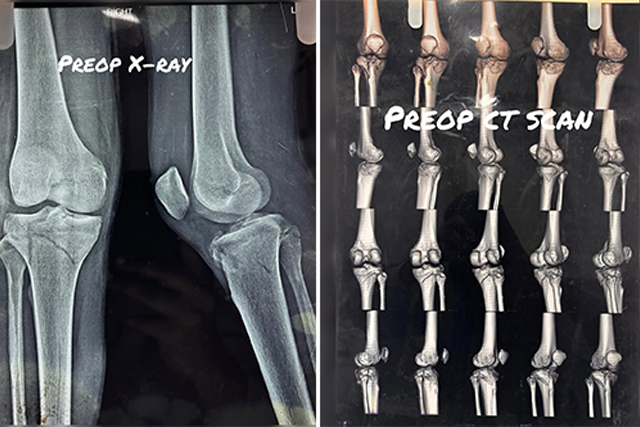

Open reduction and internal fixation (ORIF) for lateral condyle Hoffa's fracture